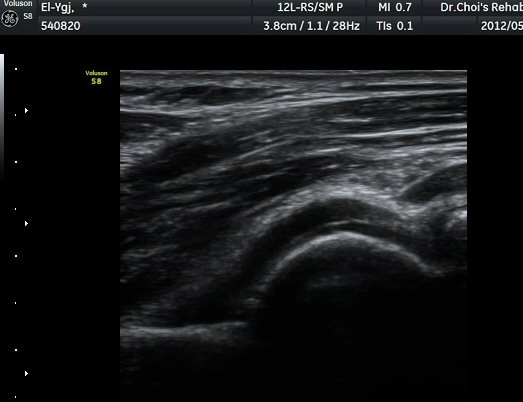

ÆÈ²ÞÄ¡ ¿ÜÃø Á¾´Ü¸é°Ë»ç¿¡¼­ ¼ÒµÎ ¾ÕÂÊ¿¡ ¼ö¾×Àú·ù°¡ °üÂûµÈ´Ù(±×¸² 1).

ÆÈ²ÞÄ¡ ³»Ãø Á¾´Ü¸é°ú Ⱦ´Ü¸é°Ë»ç¿¡¼­ ȰÂ÷ ¾Õ°ú °¥°í¸®µ¹±â¿Í(coronoid fossa)¿¡ ¼ö¾×Àú·ù°¡

°üÂûµÇ°í °¥°í¸®µ¹±â¿Í¿¡ °í¿¡ÄÚ »À µ¢¾î¸®°¡ °üÂûµÈ´Ù(±×¸² 2, 3).

ÁÖ°ü Ⱦ´Ü¸é°Ë»ç¿¡¼­ °üÀý³» ¼ö¾×Àú·ù¿Í ô°ñ½Å°æÀÇ Ç¥ÃþÀ¸·Î ÀüÀ§°¡ °üÂûµÈ´Ù(±×¸² 7).

ÁÖµÎ¿Í È¾´Ü¸é°Ë»ç ¿µ»ó¿¡¼­(»çÁø) ÃÊÀ½ÆÄ À¯µµÇÏ¿¡ °üÀý³» Áֻ縦 ½ÃÇàÇÏ¿´´Ù(µ¿¿µ»ó).